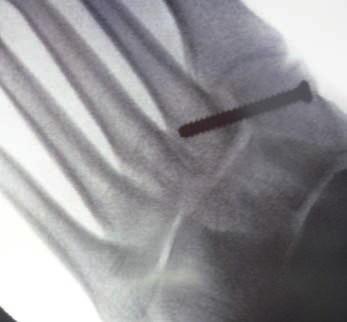

Patienten mit Verletzungen Grad II und III (n. Nunley) profitieren von einer operativen The rapie 31. Bei frischen Verletzungen gelingt meist die geschlossene Reposition durch eine Repositionszange unter Bildverstärkerkontrolle. Anschließend wird über eine kleine mediale Inzision ein Kirschnerdraht vom Os cuneiforme mediale in die MetatarsaleII-Basis gebohrt und das Lisfranc-Ligament durch eine Stellschraube in anatomischer Stellung ruhiggestellt. Durch weitere Schrauben lässt sich bei Bedarf das Tarsometatarsale-I-Gelenk und der Raum zwischen Os cuneiforme I und II stabilisieren. Nach Lagekontrolle unter dem Bildverstärker wird eine durchbohrte Schraube mit durchgehendem Gewinde eingebracht (Abb. 7). Werden Zugschrauben verwendet, kommt es zu einer unphysiologischen Kompression der Gelenkfiächen.

Kanülierte Schrauben erleichtern das Vorgehen, wobei grundsätzlich auch Standard-Kleinfragmentschrauben verwendet werden können. Die in der Literatur beschriebene Verwendung von 2,0‑mm-Kirschnerdrähten hat sich bei den Verfassern nicht bewährt. Hier besteht ein erhebliches Risiko der Lockerung und Dislokation 32. Thordarson und Hurvitz (2002) 33 berichten über den Einsatz von resorbierbaren Schrauben, Hu et al. (2014) sowie Hsu et al. (2015) über den Einsatz einer das Tarsometatarsale-I-Gelenk überspannenden Platte 34 35.